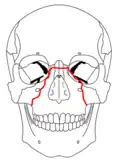

A principios del siglo XX, René Le Fort trazó ubicaciones típicas para las fracturas faciales, éstas ahora son conocidas como I, II y III fracturas de Le Fort (derecha).[5][2][6]

La fractura de Le Fort tipo II, también llamada fractura piramidal del maxilar,[7][10] cruza los huesos nasales y el reborde orbitario.[9]